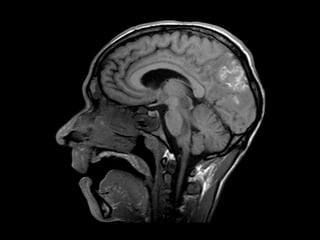

RNM de crânio: lesões multifocais supra e

infratentoriais sugestivas de processo

infeccioso/inflamatório relacionado à infecção

oportunista (neurotoxoplamose).

Demais exames sem alterações, incluindo líquor

e sorologia para toxo.

Caso Clínico RNM decrânio: lesões multifocais supra e infratentoriais sugestivas de processo infeccioso/inflamatório relacionado à infecção oportunista (neurotoxoplamose). Demais exames sem alterações, incluindo líquor e sorologia para toxo.